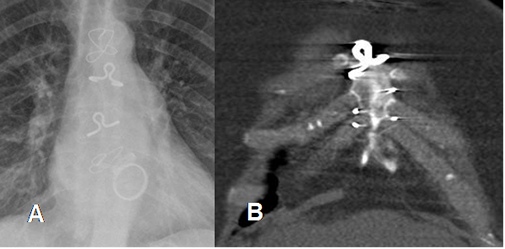

Fig 34. Cambios PostQx.

A: Rx PA y B: TAC reconstrucción coronal. Alambres de sutura sobre la topografía del esternón, después de una toracotomía para el reemplazo de válvula cardiaca.